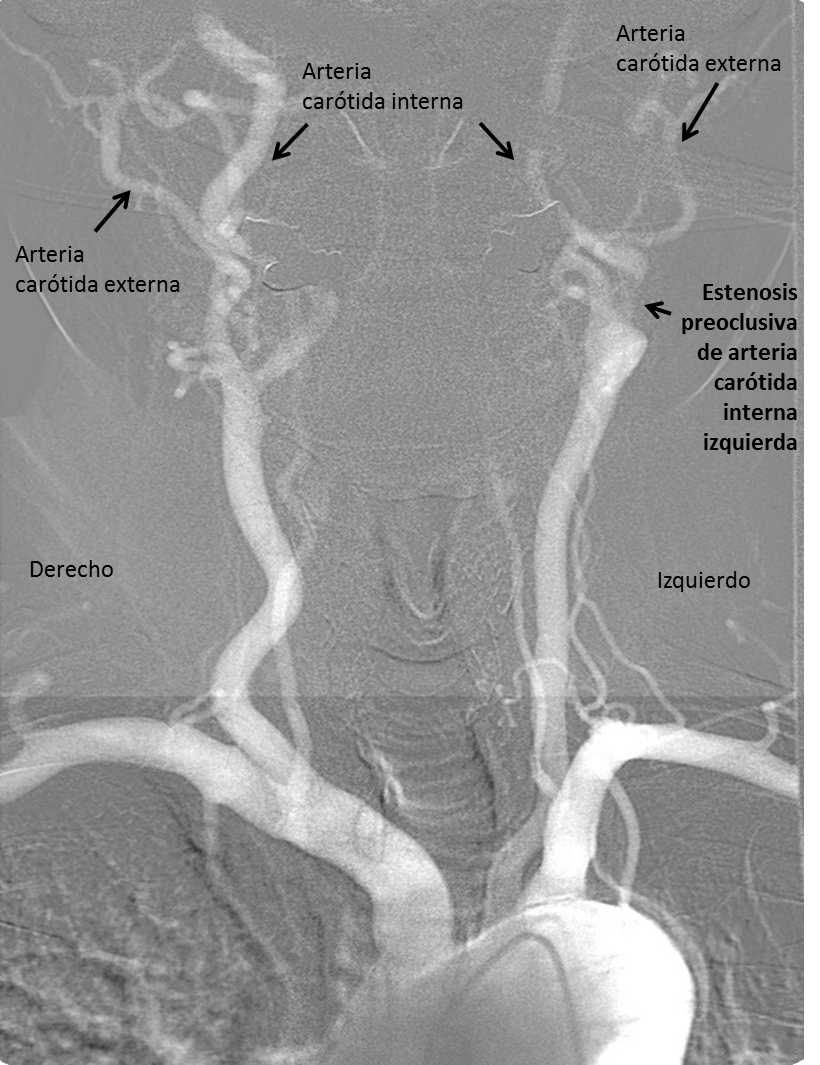

En la Imagen 2 se señalan ambas arterias carótidas internas y externas. Se diferencian en esta proyección porque la arteria carótida interna cervical no da ninguna rama. Si observamos en el lado derecho el calibre de la arteria carótida interna es mucho mayor que el de la externa mientras que en el lado izquierdo el calibre es similar. Este dato angiográfico es sugestivo de estenosis preoclusiva.

En la Imagen 3 para evitar perdernos en la proyección anteroposterior he remarcado de azul las órbitas y el cráneo. En el lado izquierdo podemos observar que se rellenan antes las ramas de la arteria carótida externa que las de la arteria carótida interna izquierda. De hecho, el contraste parece que se detiene antes de hacerse intradural. Ambos son datos angiográficos de estenosis preoclusiva. En condiciones normales, las ramas de la arteria carótida interna se rellenan antes que la externa.

En la Imagen 4. se observa que las ramas de la arteria carótida externa se rellenan de contraste antes de que se rellene la arteria carótida interna en su trayecto intradural.